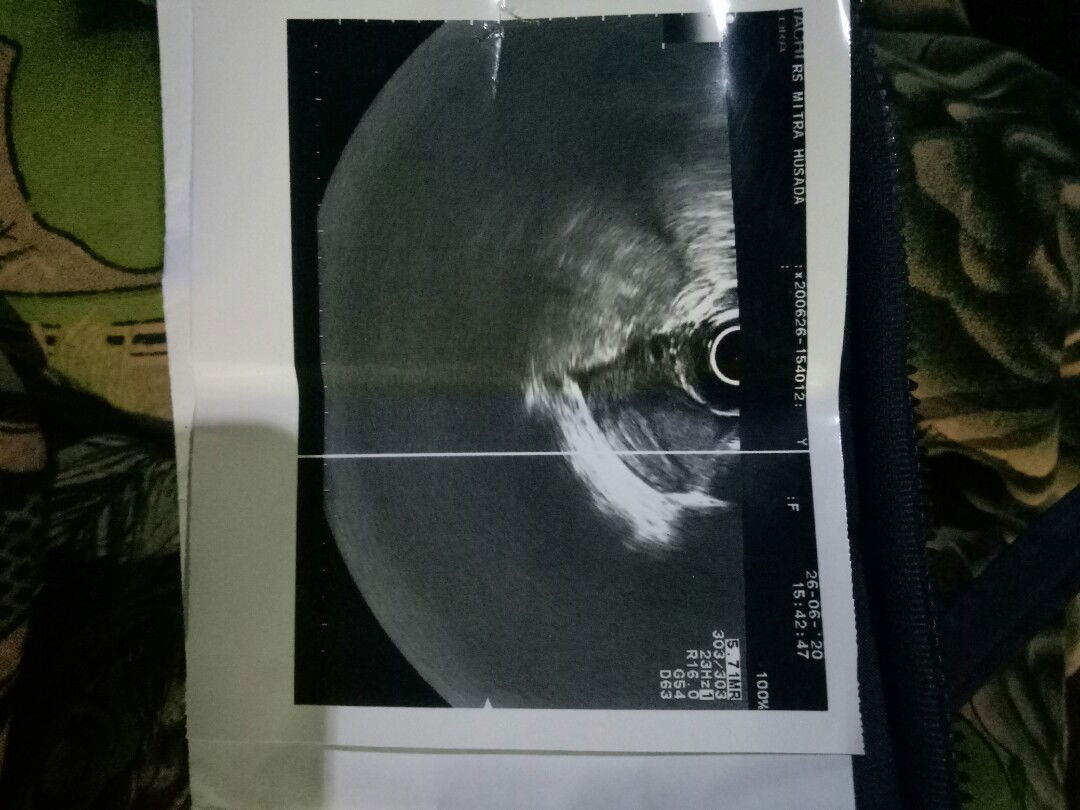

masih bingung

mom ini hasil USG saya tgl 26 pake USG transvaginal,ada yg paham gak sama foto USGnya...